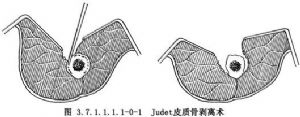

皮質骨剝離術系Judet所倡導,其方法是切口直達骨質,在骨膜下鑿去薄層骨片,但必須保持骨片與周圍軟組織的血運聯繫。皮質骨剝離範圍佔骨周徑1/2~2/3(圖3.7.1.1.1.1-0-1)。兩骨折端均須做皮質骨剝離,並使骨與其外覆蓋的軟組織之間形成袋狀,以便同時做骨折端周圍植骨(phemister bone graft)(圖3.7.1.1.1.1-0-2)。但在對位對線較好,纖維瘢痕可維持骨折端穩定時,通常是將細條形松質骨置於骨折端瘢痕周圍。對切除整新骨端而形成斷端間隙或缺損者,須用松質骨嵌入移植,以免喪失肢體長度。滑行植骨(sliding bone graft)亦稱倒置植骨,方法是在骨折端兩側切取不等長的長方形骨條,其寬度不超過骨幹周徑的1/3。將條狀骨倒置,使較長的骨塊騎跨骨折端兩側(圖3.7.1.1.1.1-0-3)。髓腔內植骨(medullary bone graft)(圖3.7.1.1.1.1-0-4)是用一側帶皮質的柱狀骨塊插入骨折端兩側髓腔內,有加強固定穩定性和促進成骨的雙重效果。長骨幹不愈合骨折用單純植骨術治療的適應證很少,一般都需同時使用堅固的內固定或外固定,爲骨癒合提供生物學和力學兩方麪條件。